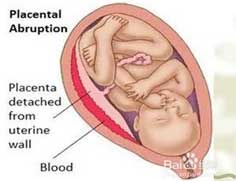

盆腔器官脱垂(POP)

疾病介绍:指盆腔器官脱出于阴道内或阴道外。阴道前壁脱垂也即阴道前壁膨出,阴道内2/3膀胱区域脱出称之膀胱膨出。若支持尿道的膀胱宫颈筋膜受损严重,尿道紧连…【详细】